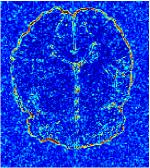

All the experiments are implemented on a Windows workstation with Intel Core i9 CPU at 3.3GHz and an Nvidia GTX-1080Ti GPU with 11GB of graphics card memory via TensorFlow Abadi et al. (2016). The parameters in the proposed network are initialized by using Xavier initialization Glorot and Bengio (2010). We trained the meta-learning network with four tasks synergistically associated with four different CS ratios: 10%, 20%, 30%, and 40%, and test the well-trained model on the testing dataset with the same masks of these four ratios. We have 300 training data for each CS ratio, which amount to total of 1200 images in the training dataset. The results for and MR reconstructions are shown in Tables 5.4 and 5.4 respectively. The associated reconstructed images are displayed in Figures 1 and 3. We also test the well-trained meta-learning model on unseen tasks with radio masks for skewed ratios: 15%, 25%, 35%, and random Cartesian masks with ratios 10%, 20%, 30% and 40%. The task-specific parameter for the unseen tasks are retrained for different masks with different sampling ratios individually with fixed task-invariant parameters . In this experiments, we only need to learn for three skewed CS ratios with radio mask and four regular CS ratios with Cartesian masks. The experimental training proceed on less data and iterations, where we performed on 100 MR images with 50 epochs. For example, for reconstructing MR images with CS ratio 15% radio mask, we fix the parameter and retrain the task-specific parameter on 100 raw data with 50 epochs, then test with renewed on our testing data set with raw measurement that sampled from radio mask with CS ratio 15%. The results associated with radio masks are shown in Table 5.4 and 5.4, Figure 2 and 4 for and images respectively. The results associated with Cartesian masks are list in Table 5.4 and reconstructed images are displayed in Figure 5.

In this section, we test the generalizability of the proposed model that tests on unseen tasks. We fix the well-trained task-invariant parameter and only train for sampling ratios 15%, 25% and 35% with radio masks and sampling ratios 10%, 20%, 30% and 40% with Cartesian masks. In this experiment, we only used 100 training data for each CS ratio and apply a total of 50 epochs. The averaged evaluation values and standard deviations are listed in Table 5.4 and 5.4 for reconstructed T1 and T2 brain images respectively that proceed with radio masks, and Table 5.4 shows the qualitative performance for reconstructed T2 brain image that applied random Cartesian sampling masks. In T1 image reconstruction results, meta-learning improved 1.6921 dB in PSNR for 15% CS ratio, 1.6608 dB for 25% CS ratio, and 0.5764 dB for 35% comparing to the conventional method, which in the tendency that the level of reconstruction quality for lower CS ratios improved more than higher CS ratios. A similar trend happens in T2 reconstruction results with different sampling masks. The qualitative comparisons are illustrated in Figure 2, 4 and 5 for T1 and T2 images tested in skewed CS ratios in radio masks, and T2 images tested in Cartesian masks with regular CS ratios respectively. In the experiments that conducted with radio masks, meta-learning is superior to conventional learning especially at CS ratio 15%, one can observe that the detailed region in red boxes keeps edges and is more close to the true image, while conventional method reconstructions are hazier and lost details in some complicated tissue. The point-wise error map also indicates that Meta-learning has the ability to suppress noises.